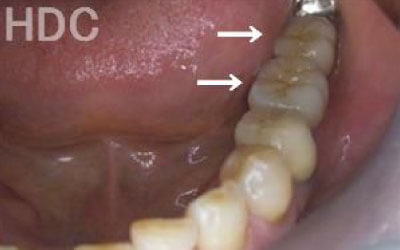

2 歯が傾いてくる、落ちてくる

歯は互いに支え合ってバランスを保っています。つまり、歯が抜けるとその支えがなくなり、抜けた部分の隣の歯が倒れたり、上の歯が下に沈んだりすることがあります。